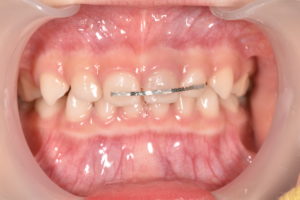

受傷から1ヶ月半

少し歯の変色は残っていますが、元の色に戻ってきました。

痛みもなく、レントゲン所見も異常がないため、固定していたワイヤーを除去し更に経過観察を行います。